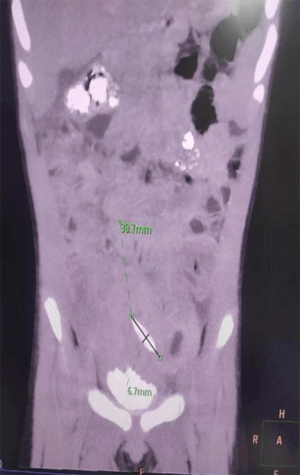

8月7日,一位2岁孩子因“间断发热伴腹痛17天,腹泻5天”入住宝鸡市妇幼保健院儿童医院儿童消化营养科,入院初步诊断为感染性腹泻,经2日抗感染、补液等对症治疗,但不见疗效。儿童消化营养科主任唐红强、副主任医师刘敏宁等专家会诊后发现问题没有那么简单,在完善腹部增强CT检查后结果出乎所有人意料:在患儿腹部有粒长约3.0cm的枣核,且已经穿孔并将部分肠管串联在一起,患儿乙状结肠至直肠段水肿严重。

查明病因后医院多学科联合诊疗机制启动,小儿外科积极参与会诊并制定了手术方案,术中见到下腹肠管与盆腔及左髂窝粘连紧密,触及一两端坚制硬物,明确枣核入腹腔,并见乙状结肠、降结肠与周围肠管、腹膜广泛粘连,可见粪汁及较多坏事组织,发现结肠有长约1.0cm破口。手术团队取出来患儿枣核,修补了破损粘连的组织,目前患儿正在稳定恢复中。